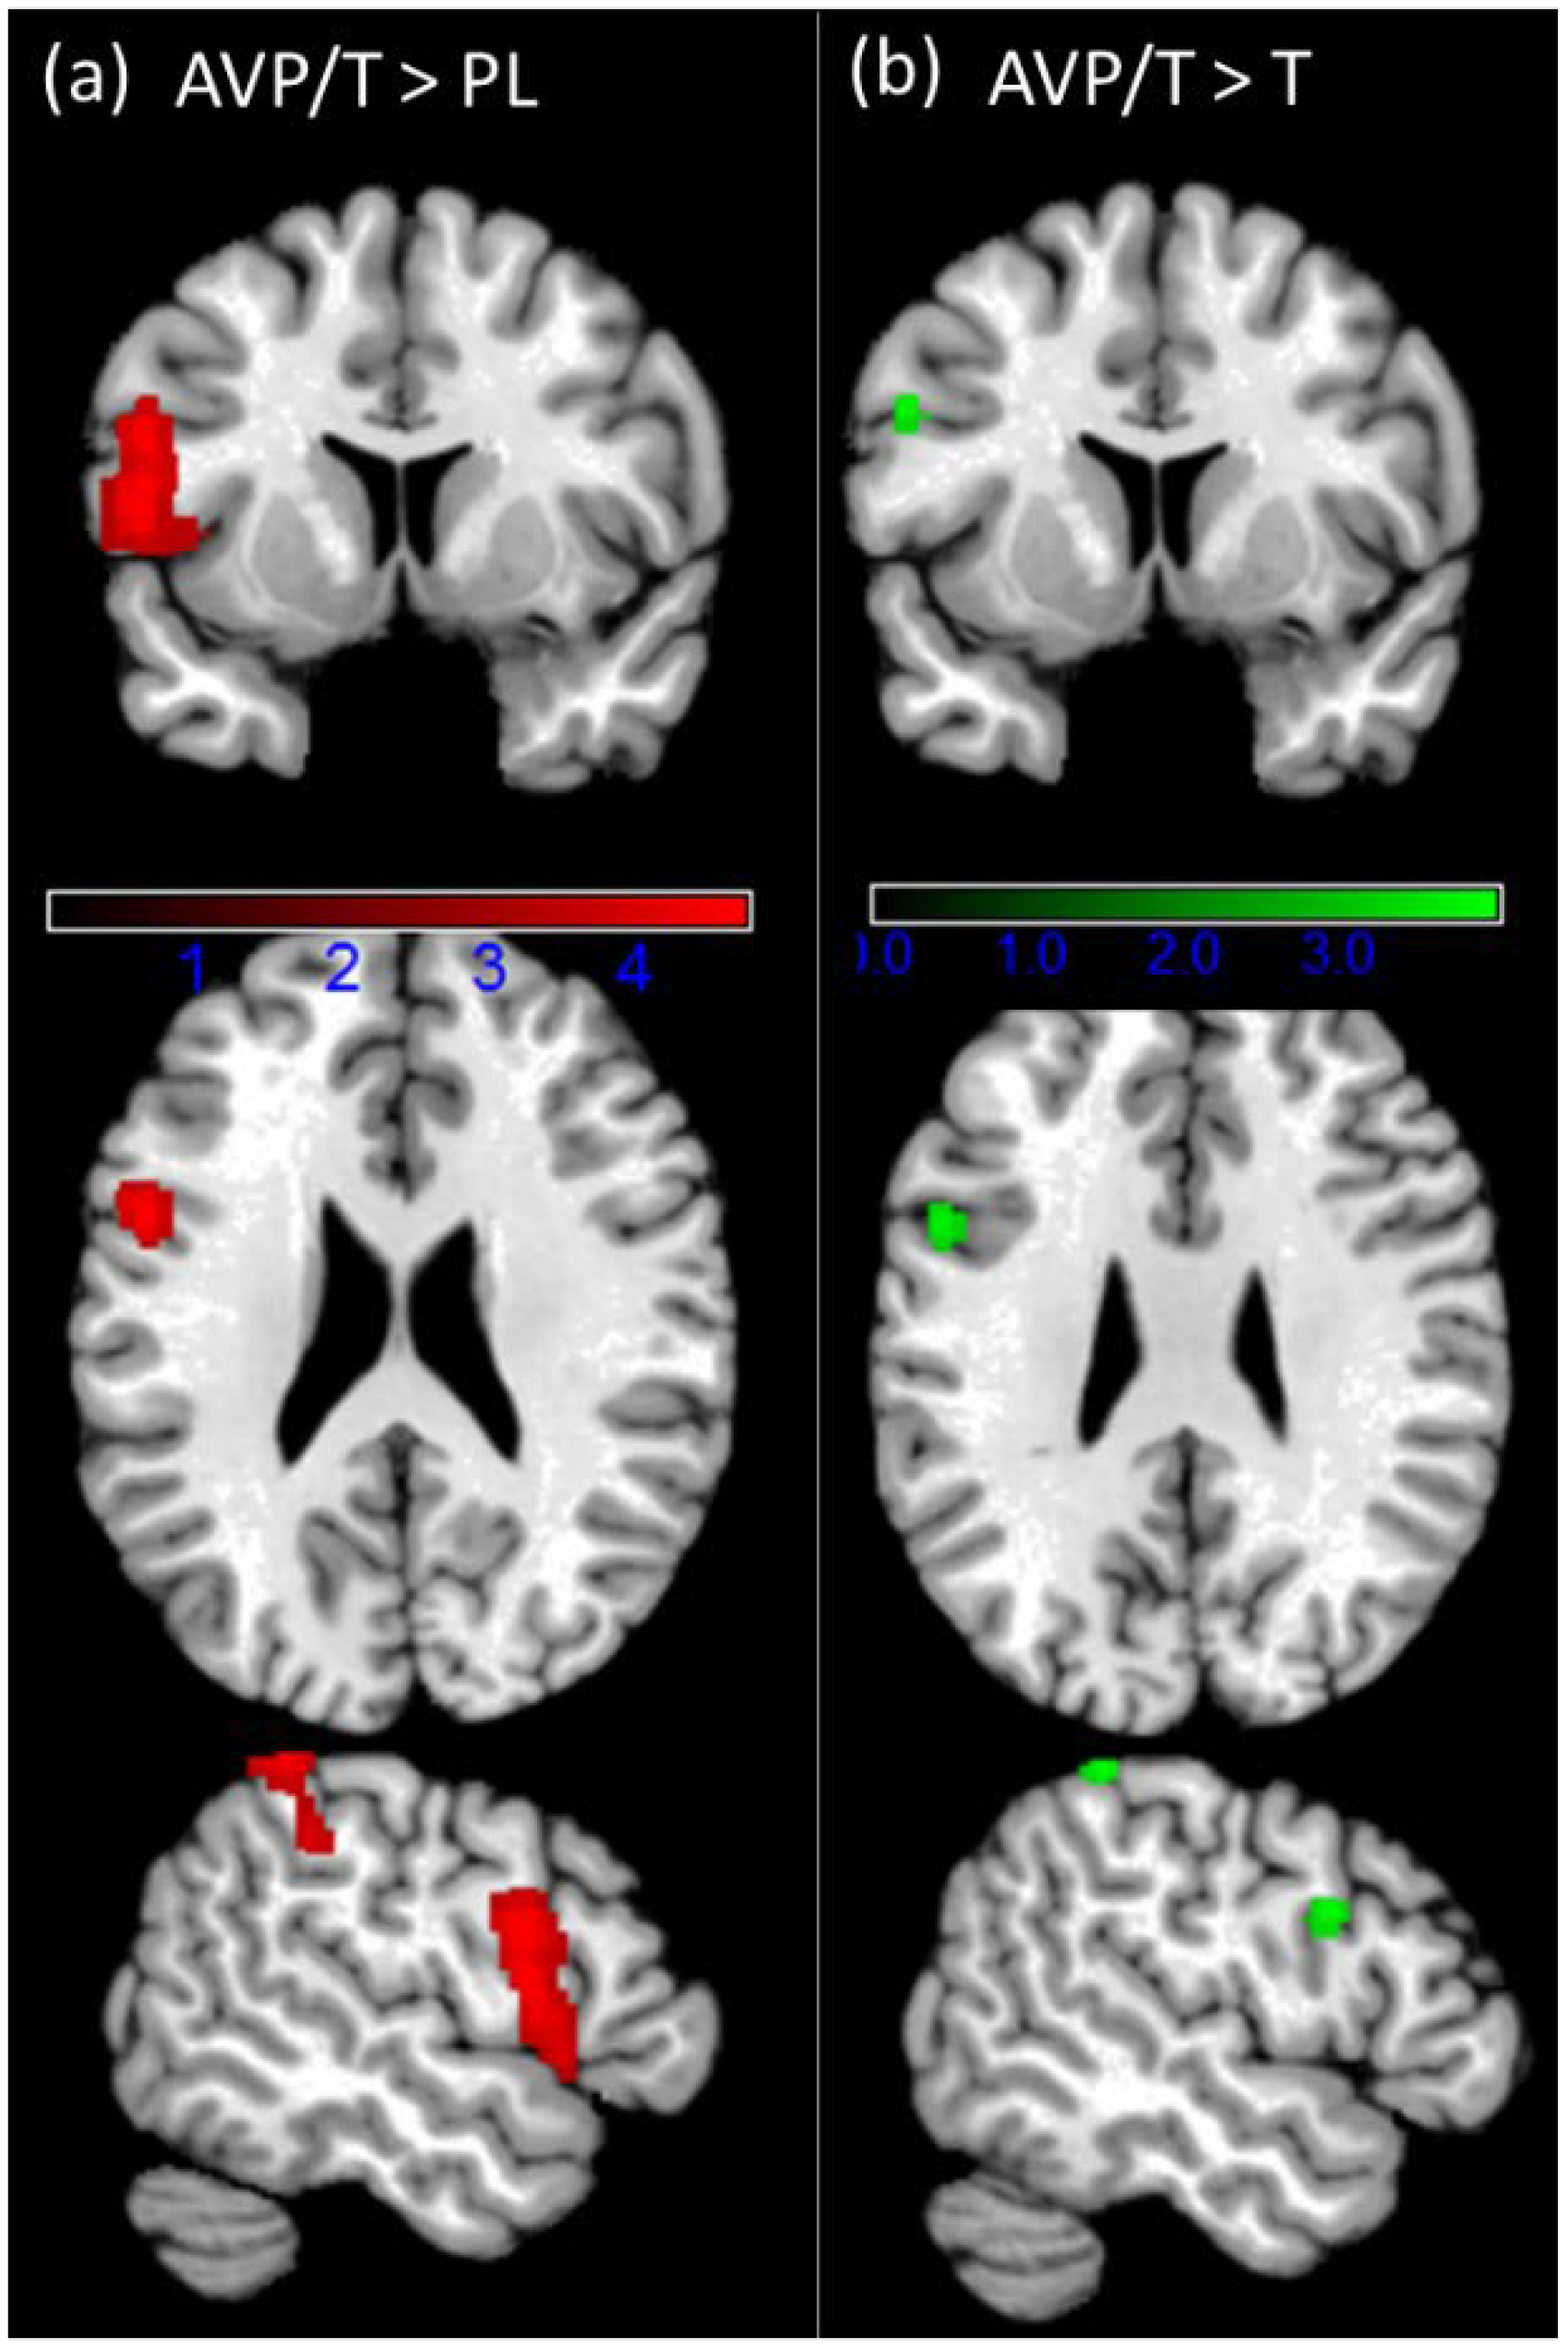

3.4. fMRI Results

4.2. Hormonal Modulation of Brain Signals